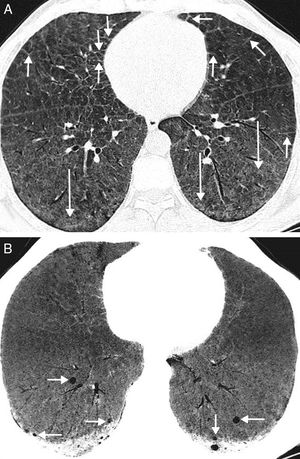

During a follow-up computed tomography (CT) in a 46-year-old patient with Niemann-Pick type B disease (NPBD) diagnosed during childhood, we detected bilateral pulmonary cysts and interstitial lung disease consisting of diffuse thickening of the interlobular septa and areas of ground glass attenuation (Fig. 1A). The pulmonary cysts were small, and located mainly in the middle and lower fields of both lungs (Fig. 1B). From a clinical point of view, the patient presented hepatosplenomegaly and dyspnea on exertion, with no neurological involvement. Lung function tests were normal, except for a slight decrease in CO diffusing capacity.

(A) Axial CT image of the chest (pulmonary parenchymal window) showing thickening of interlobular septa (short arrows) and areas of ground glass attenuation (arrows). (B) Minimum intensity projection (MinIP) axial CT image of the chest (pulmonary parenchymal window) showing small lung cysts in the basal segments of both lower lobes (arrows).